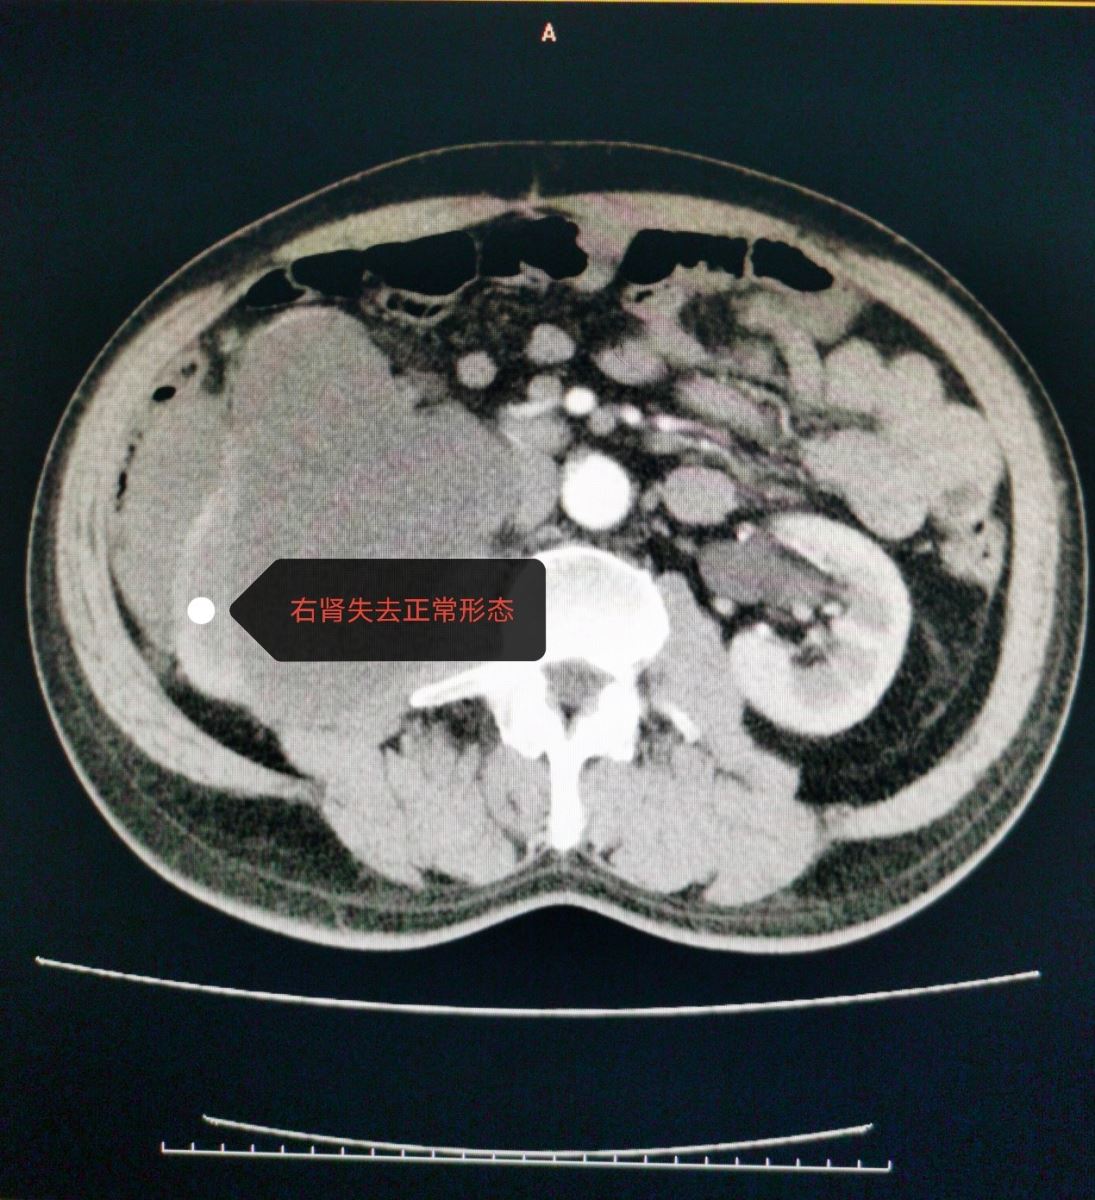

近日,西院肿瘤外科成功为一腹膜后脂肪肉瘤复发患者开展手术。患者于1年半前在外地某三甲医院被诊断为“腹膜后肿物”,行腹膜后肿物切除术,术后病理诊断为“腹膜后脂肪肉瘤”。此后定期复查,1月前,患者自觉左侧腹部可触及包块,伴疼痛,腹胀,食欲下降,消瘦明显。在外院查腹部彩超提示:腹膜后肿物。患者为进一步治疗,来我院。入院后完善检查,进一步明确诊断。全腹增强CT提示:右中腹见团块状混杂密度影,形态不整,右肾变形,内部密度不均,与下腔静脉、胰头、十二指肠,右侧腰大肌关系密切,增强扫描呈混杂密度影。肿瘤外科全体医生对患者病情进行了细致详尽的术前讨论。患者1年半前行腹膜后脂肪肉瘤切除术,此次考虑为腹膜后脂肪肉瘤复发,肿瘤较大,与周围器官关系密切,尤其紧邻下腔静脉,二次手术风险极大,一旦发生下腔静脉意外撕裂,可能造成空气栓塞等致命性危险。全科医生一起反复仔细查阅增强CT,制定详尽的手术计划。并对可能出现的风险及意外进行预判,提出解决方案。与患者家属沟通,详细交待病情,说明治疗方案及手术风险。

在进行了充分的围手术期准备后,手术如期进行,手术由张凤祥院长、刘德智主任、郭云峰医生、包巴特尔医生共同完成。术中探查所见:肿瘤位于右侧腹腹膜后,上方达肝下缘并伸向后纵膈,下方达右侧髂窝水平,内侧包绕下腔静脉前后方,外侧达升结肠侧腹壁,前方侵犯右半结肠系膜,后方与右侧腹膜后广泛粘连,右肾及肾血管、右输尿管包裹于肿瘤中。术中考虑为腹膜后脂肪肉瘤复发,决定行腹膜后脂肪肉瘤联合右半结肠、右肾、右肾上腺切除。肿物与周围组织器官粘连致密,活动度差,切除极其困难。手术历时四个半小时,顺利将腹膜后肿瘤与右半结肠、右肾上腺、右肾一并完整切除。未出现副损伤,患者术后恢复良好。